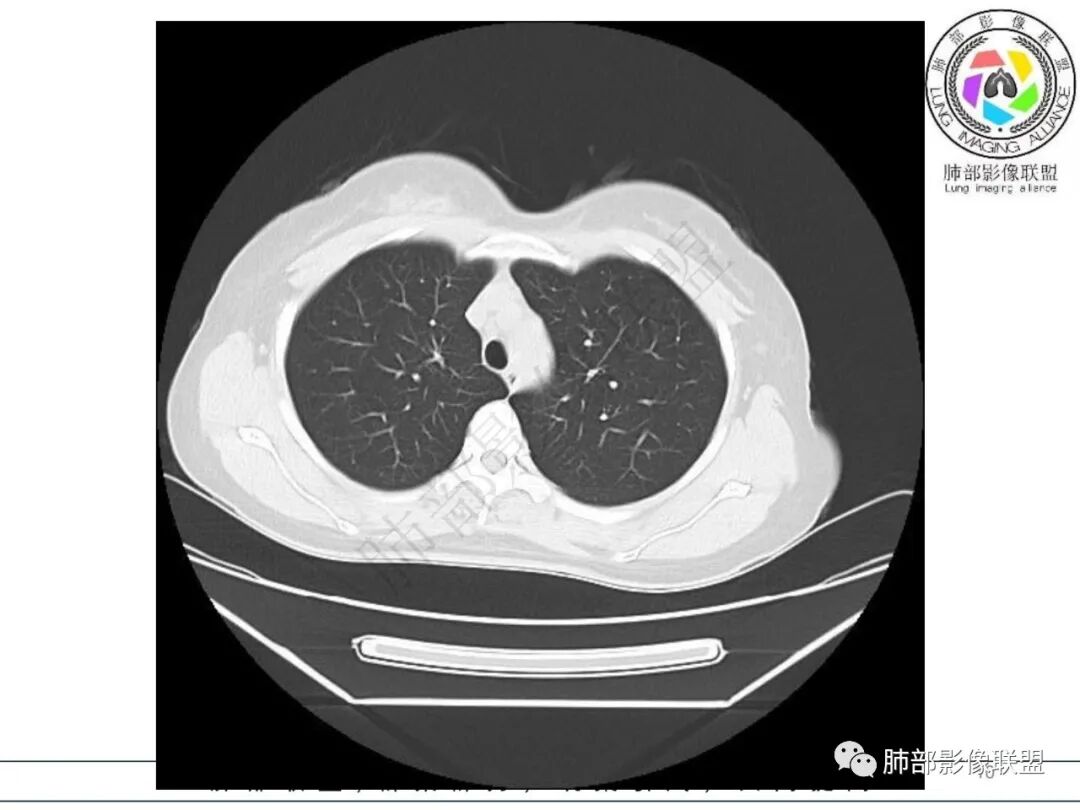

年轻女性,发热,白细胞略低,超敏CRP高,右肺下叶团片影,边缘毛糙,周围见磨玻璃晕,其内含气细支气管,考虑炎性肉芽肿,侵袭性曲霉菌感染?鉴别淋巴瘤

年轻,急性起病,发热伴肺部阴影,考虑感染性病变没问题,无诱因,还是真无诱因,咳嗽无痰,有一些胃肠道症状及乏力。肺部一斑片影,考虑非典型病原菌,治疗无效考虑下特殊病原。这个病程3天,渗出不明显,周围磨玻璃感觉蛮清晰,支气管充气征?鉴别淋巴瘤?

右肺下叶局限性实变影伴晕征。

女,34,畏寒、发热3天,伴纳差、恶心、呕吐。血像不高,ESR、CRP增高。胸部CT:右肺下叶局限斑片影,边缘模糊,内可见支气管穿行,个别层面融冰?肺动脉貌似增粗,考虑不典型病原体感染?肺梗?鉴别淋巴瘤等。

2.影像特征:右肺下叶局限性实变影伴晕征,边界不清,内部支气管尚通畅,实变区密实区边缘稍膨隆。符合炎性病灶特征。